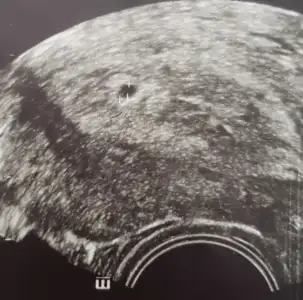

Kese gozukur aslinda alltan.Günaydın , 1826 dan 2904 e yükselmiş beta %60 civarı

%63 falan oluyor gayet iyi bence.Günaydın , 1826 dan 2904 e yükselmiş beta %60 civarı

Kese 4000 falan olunca üstten görülür diğer şekilde alttanNasıl yani kese görmeye gideceğimiz zaman gene normal alttan muayene mi yapıyorlar

Usttende gorulüyor bi sure sonra canimNasıl yani kese görmeye gideceğimiz zaman gene normal alttan muayene mi yapıyorlar